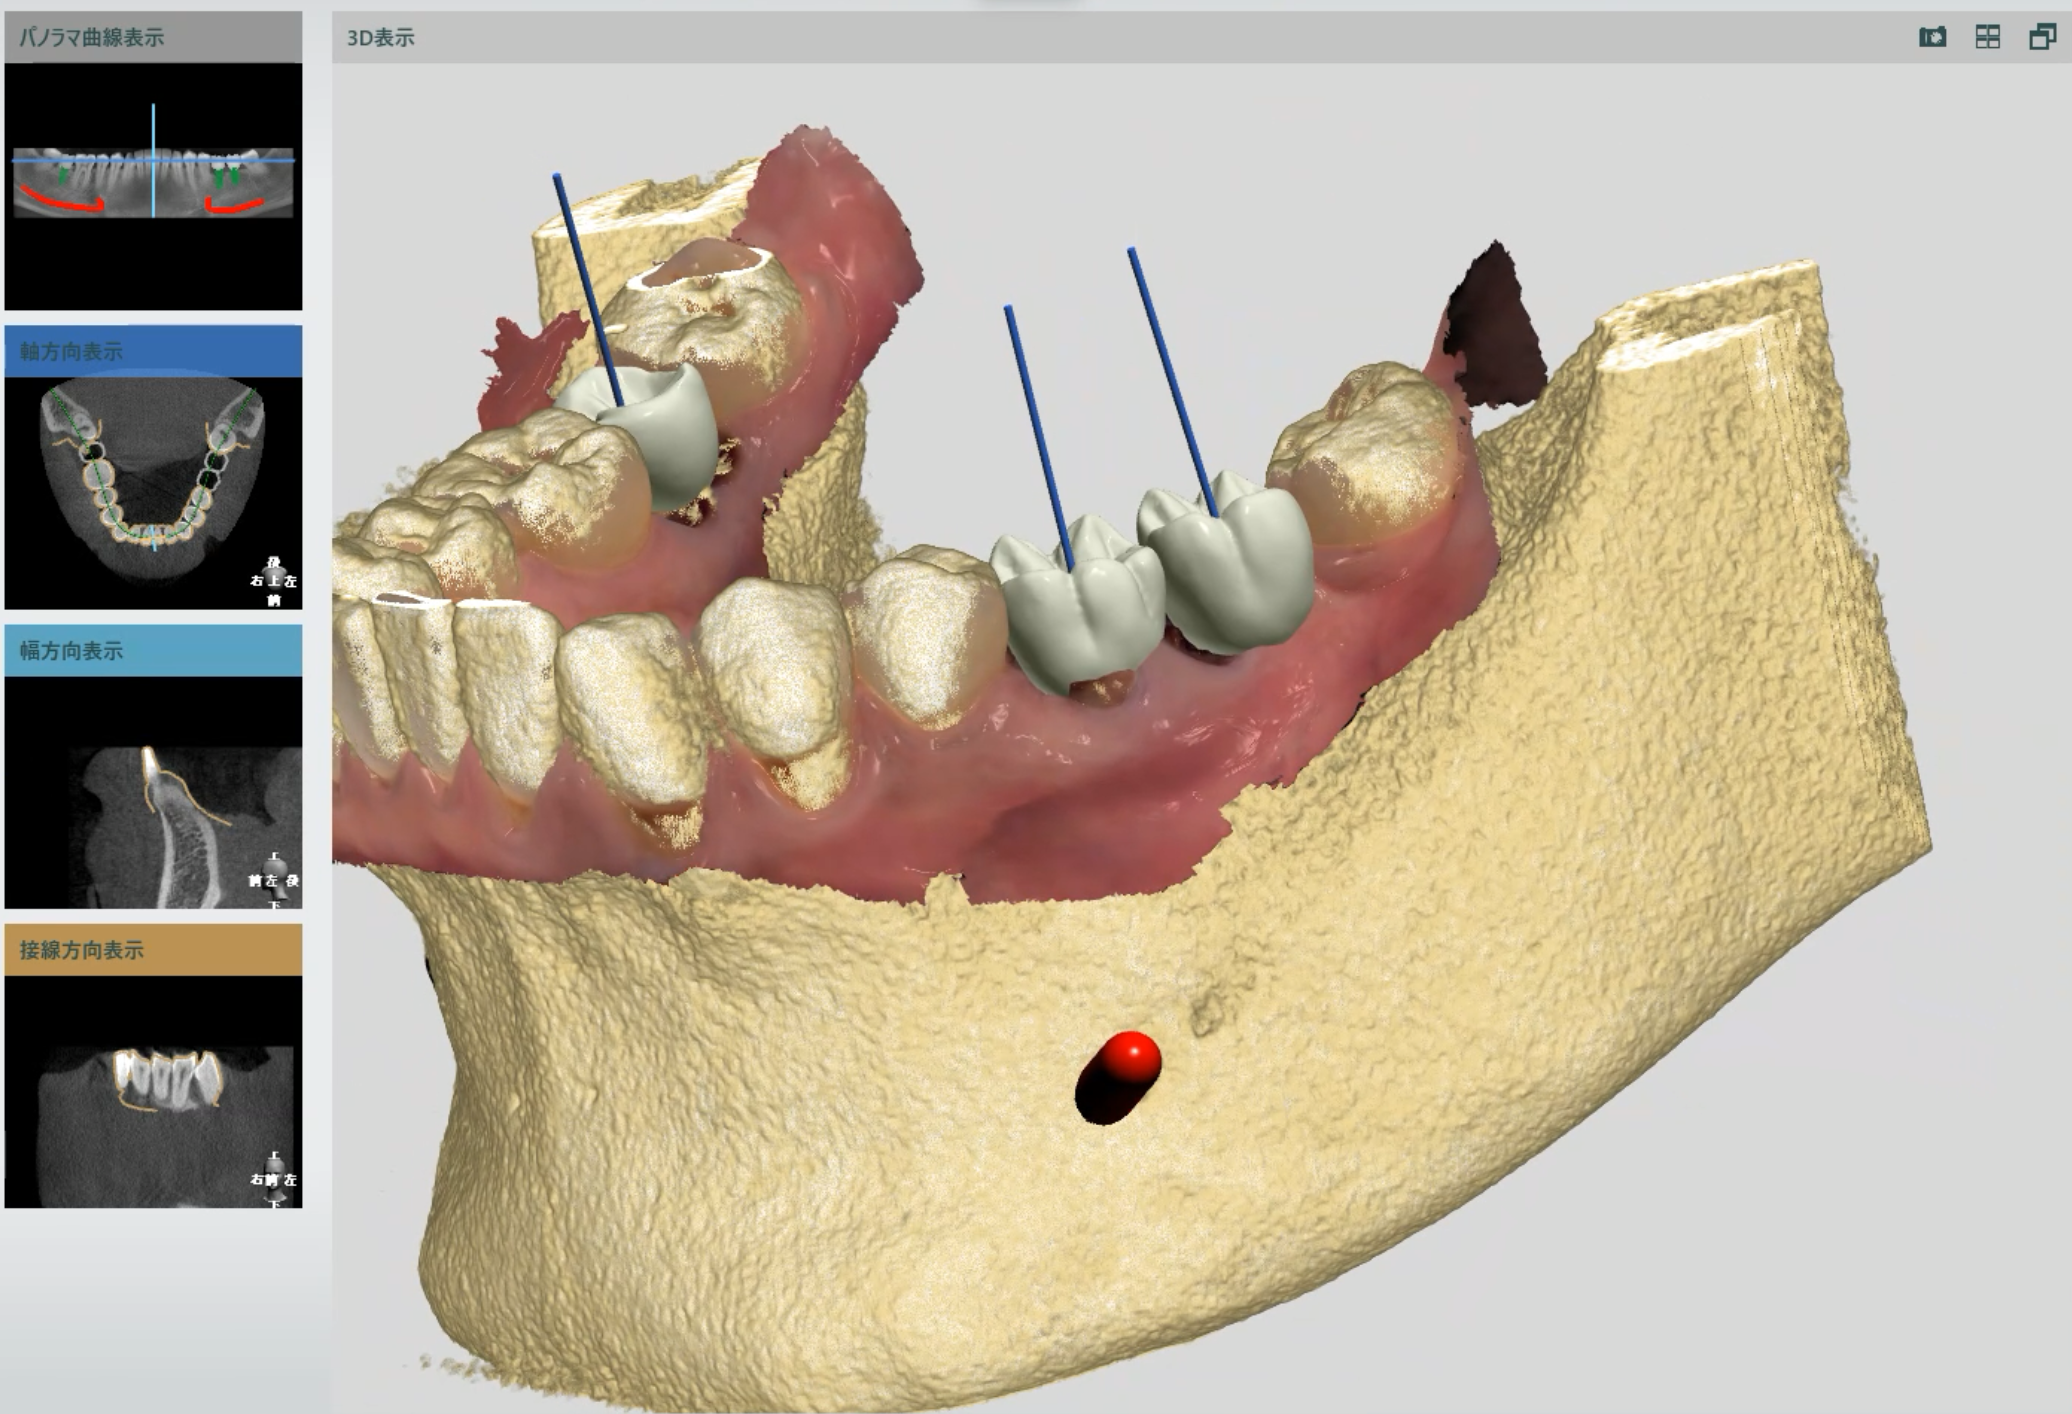

- デジタル画像診断(将来の歯を想定し、インプラントの埋入計画を立体視)